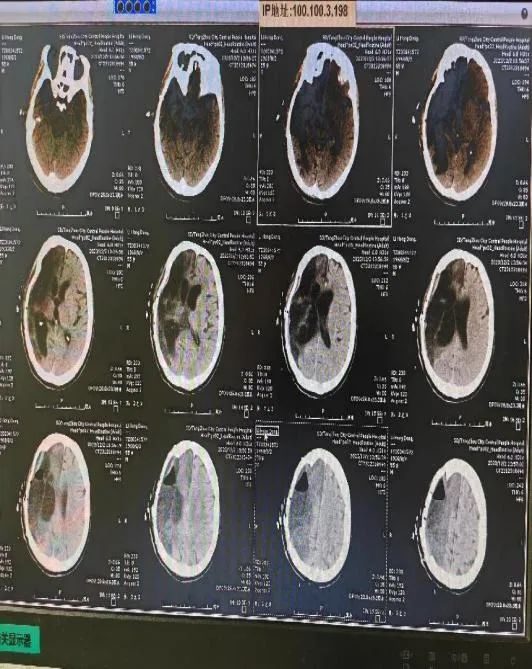

患者,男,55歲,因“開(kāi)顱術(shù)后顱骨缺損4月余”就診,CT提示“右側(cè)額顳頂部分顱骨缺損、大面積腦梗塞術(shù)后改變”,以“右側(cè)額顳頂部分顱骨缺損、大面積腦梗塞術(shù)后”收入院。經(jīng)積極完善術(shù)前檢查,李永濤主任、王亞文護(hù)士長(zhǎng)、吳超副主任組織科室醫(yī)護(hù)人員討論,認(rèn)為患者顱骨缺損修補(bǔ)手術(shù)明確,決定行“改良顳肌重建應(yīng)用于顱骨缺損修補(bǔ)術(shù)”。

12月1日,經(jīng)周密術(shù)前準(zhǔn)備,在手術(shù)室護(hù)理團(tuán)隊(duì)及麻醉團(tuán)隊(duì)協(xié)作下,吳超副主任醫(yī)師、趙曰琨主治醫(yī)師歷經(jīng)2個(gè)小時(shí),成功為該患者完成了“顱骨缺損修補(bǔ)+改良顳肌重建術(shù)”,現(xiàn)恢復(fù)良好。術(shù)后復(fù)查顱腦CT情況良好。